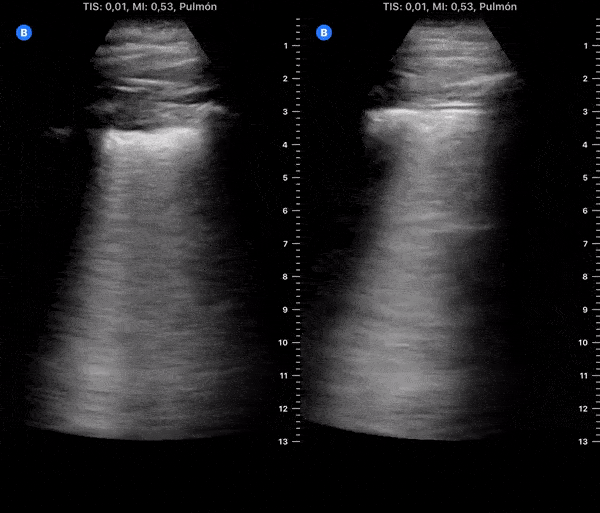

COVID 19 Lung US Disease Progression - Day 5

Day 5 after #COVID diagnosis. Less cough & tired, still no dyspnea/chest pain. #POCUS update: Effusion resolved, as subpleural consolidations spread bilaterally on both posterior lower lobes. @yaletung